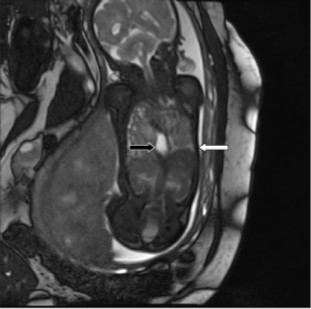

Charts were retrospectively reviewed for observed-to-expected (O/E) values for U/S LHR, MRI FLV measurements, and outcome of the pregnancy and fetus. O/E values normalize measurements to the gestational age of the fetus. MRIs were also retrospectively reviewed by a single pediatric radiologist for location of the stomach. Stomach location was simply defined as all, some, or none of the stomach in the thorax (Figure 2). The primary outcome was survival to discharge. Ultrasound O/E LHR and MRI O/E FLV was compared for all fetuses. An U/S LHR < 1, U/S O/E LHR < 15%, and MRI O/E FLV <25% were considered predictors of poor outcome, and these values were utilized to determine if the various measurements correlated.

Figure 2.MRI demonstrating the entire fetal stomach (black arrow) in the thoracic cavity. The white arrow points to the fetal diaphragm.

Of the 19 patients, 4 had none or some stomach in the thorax on MRI. All 4 of these patients survived until discharge. Fifteen patients had all their stomach in the thorax on MRI. These patients had significantly lower U/S LHR, U/S O/E LHR ,and MRI O/E FLV (Table 3). Only 21% of these patients survived.

Since none of these typical prognosticators are ideal and other measurements such as the McGoon index are also complex to obtain, we investigated simply using stomach position on MRI as a prognostic indicator. The location of the stomach serves as a marker of defect size, visceral herniation, and pulmonary hypoplasia. Here we report that those patients with some or no stomach in the thorax have significantly higher U/S LHR, U/S O/E LHR, and MRI O/E FLV than those with all of their stomach in the chest. Furthermore, all patients who had just some or no stomach in the chest on MRI survived to surgery and discharge. Therefore, lack of the entire stomach in the thorax on MRI is a good prognostic indicator.

The stomach position on MRI matched the expected outcome in 15/ out of 19 (78.9%) patients, while U/S LHR, U/S O/E LHR or MRI O/E FLV matched the expected outcomes in 13/19 (68.4%) patients. These 13 patients were not the same patients in all groups. While there was not a statistical difference between the ability of stomach position on MRI to predict outcome compared to U/S LHR, U/S O/E LHR, or MRI O/E FLV (p=0.71 for all comparisons), stomach position on MRI is not inferior as a prognostic indicator in CDH for this cohort of patients. Stomach position on MRI also has the advantage that it is quick and easy to obtain by a radiologist without specific fetal expertise. We propose that this finding be utilized in addition to, or as an alternative of for more complex and less reproducible measures.